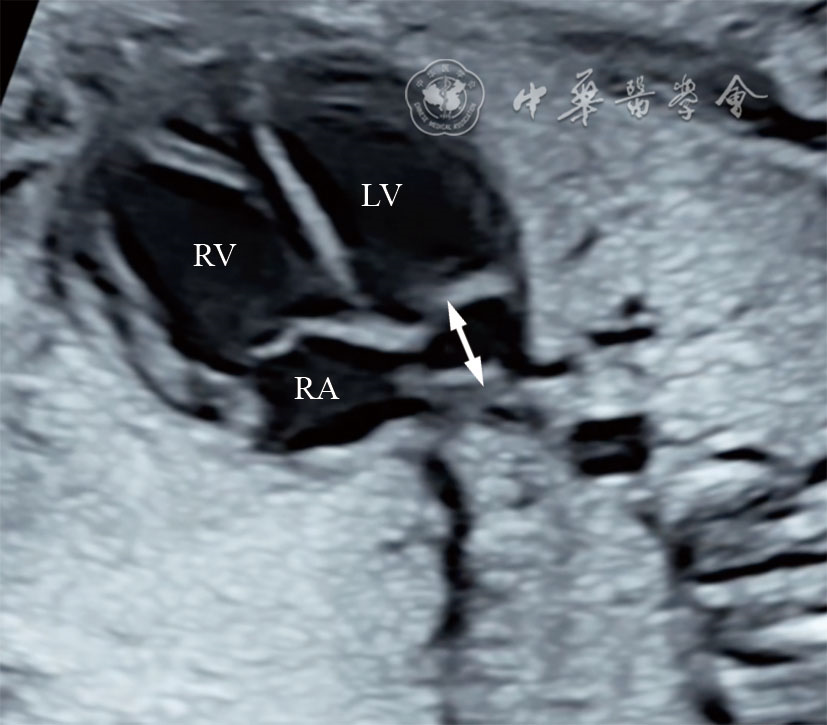

图5 二维超声图像显示四腔心斜切面房室沟处扩张的冠状静脉窦(双向箭头所示) 注:RV为右心室;LV为左心室;RA为右心房